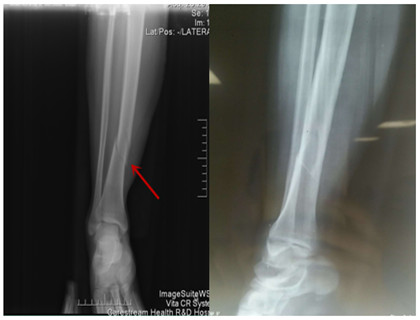

我院首例胫骨骨折MIPPO技术